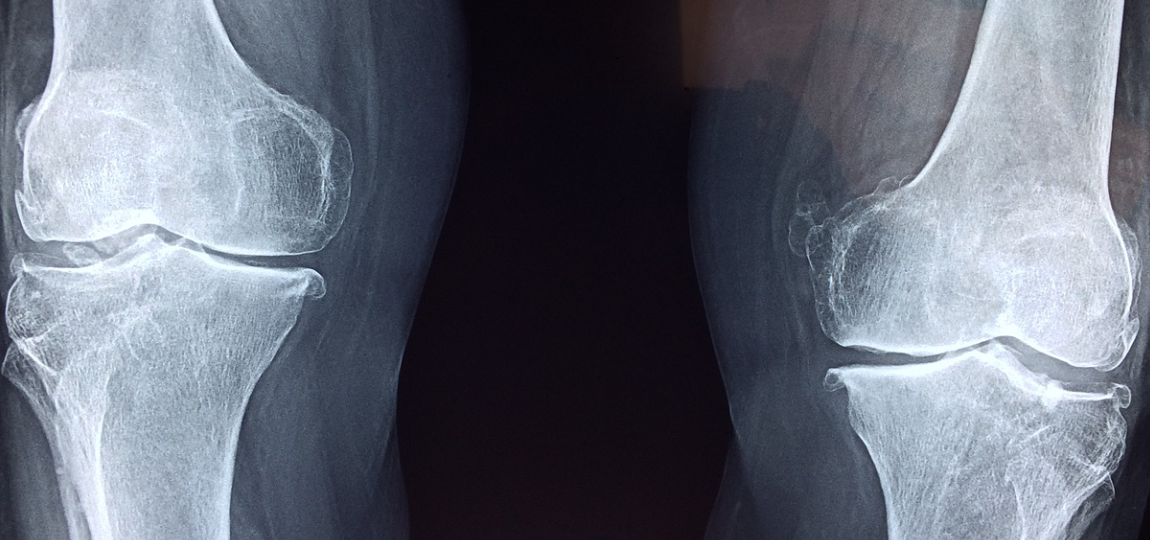

1) 관절 및 연골 통증, 기능 개선

골관절염에 해당하는 퇴행성 관절 질환, 퇴행성 관절염은 뼈와 관절막 주변 인대의 손상이 일어나 통증이 발생하게 됩니다. 증상을 개선하는데 콘드로이친이 위약보다 우수해 기능과 통증을 개선하는데 도움이 된다는 연구 결과가 발표되었습니다.

콘드로이친은 연골 파괴의 원인이 되는 효소 활동을 억제해 연골 손실슬 예방하는 효능이 있습니다. 장기 섭취 시 손상된 연골이 개선되었다는 연구 결과가 보고되었습니다.

2) 관절염 붓기 완화

콘드로이친은 관절염으로 인한 부종을 완화시키는 것으로 나타났습니다.

콘드로이친을 꾸준히 섭취한 결과 전반적인 운동 능력뿐 아니라 근육을 강화해 무릎 골관절염 치료에 효과적인 것으로 나타났습니다.